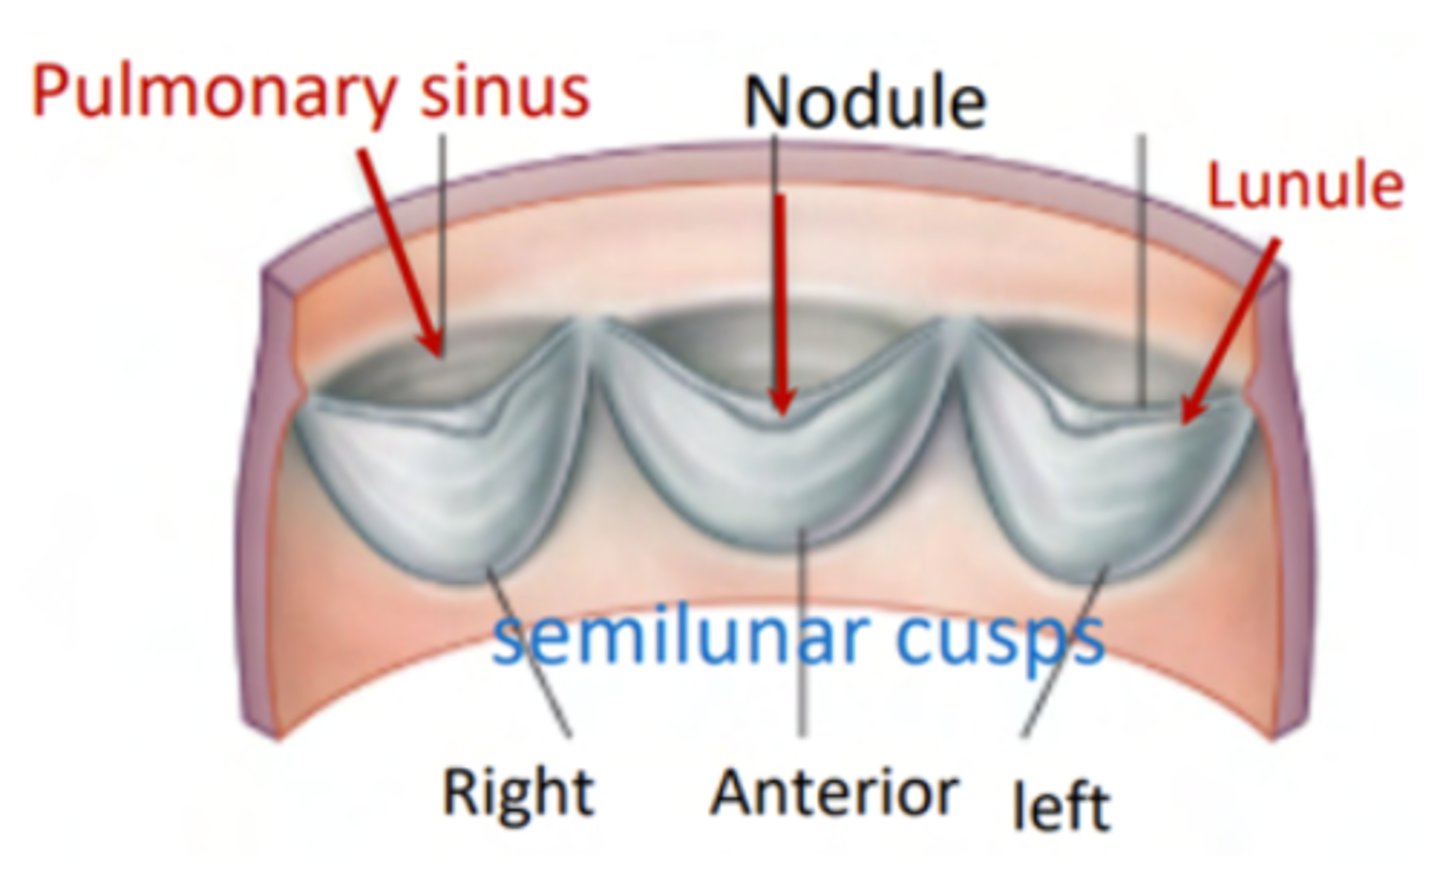

What are the positions of the pulmonary valve cusps?

Anterior

Right

Left

What are the 3 parts of the pulmonary valve?

. Nodules. (little point at the center)

. Lunules (from the nodule to the wall)

. Sinus (left in between)